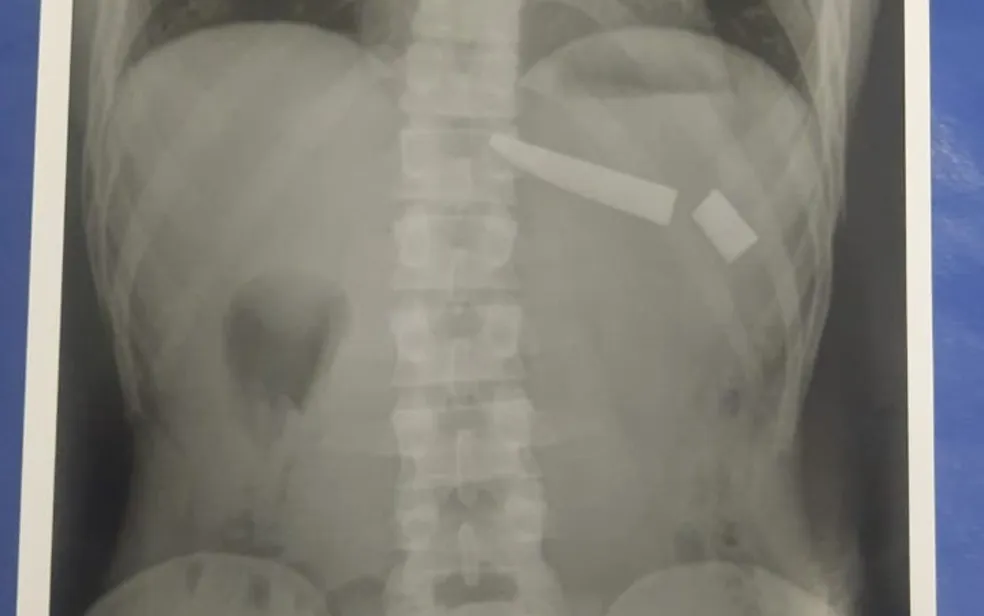

Faca quebra dentro do tórax de jovem durante briga com vizinho que tentava intervir em discussão de casal

Jovem que foi esfaqueado precisou passar por cirurgia. Suspeito disse que o atingiu nas costas e na região dos rins. Um jovem de 25 anos precisou passar por cirurgia nesta quarta-feira (4) após uma faca quebrar dentro dele, em Goiânia. Segundo a Polícia Militar, ele estava brigando com a esposa quando um homem interveio e eles […]